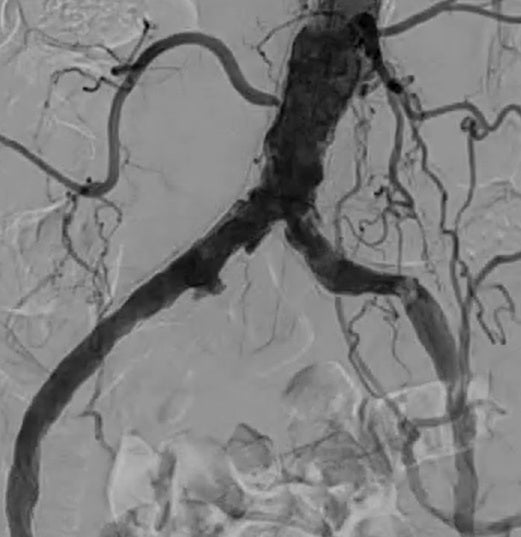

最終造影画像

左 CIA 起始部および左 EIA 起始部の高度石灰化結節による高度狭窄病変のため、バルーン拡張型ステントグラフトが最適な病変である。両鼠径部の経皮的穿刺に難があり維持透析中の症例であるが、右前腕動静脈シャントは長期間安定しており、また、左橈骨動脈が血管径3 mmと良好であったため、左橈骨動脈穿刺に問題なしと判断した。6 Fr 110 cmのガイディングシースを使用し、0.018 inch ガイドワイヤーにて病変通過後、5.0 × 100 mmバルーンにて前拡張を行い(図1)、バルーンアンカー法にてガイディングシースを病変通過させた。0.035 inch ガイドワイヤーに交換後、VBXステントグラフト7.0 × 59 mm を左 CIA 起始部から左 EIA にかけて留置した(図2、3)。拡張不良部を7.0 × 20 mm のhigh pressure 対応バルーンにて後拡張した(図4)。最終造影で確認し穿刺部を橈骨動脈用の止血用押圧器具にて止血し手技を終了した。手技時間は 40 分であった。